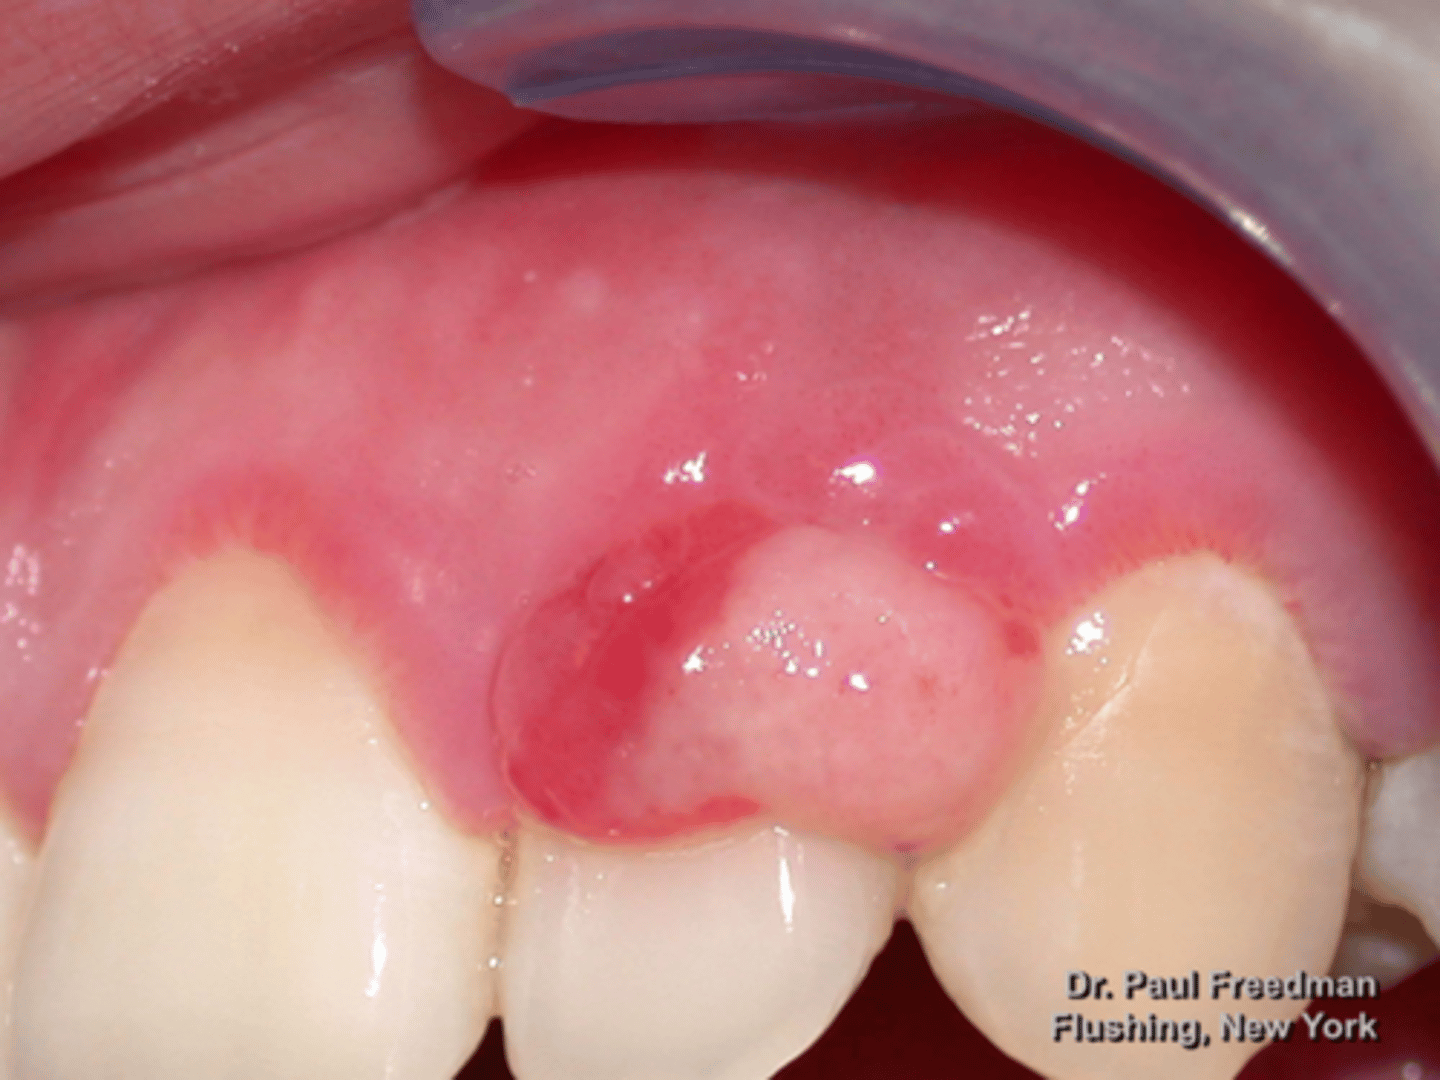

Peripheral Ossifying Fibroma

patient presents with pink nodule on the facial aspect of the mandibular gingiva. Histopathology shows fibrous proliferation with formation of mineralized (osseous) product. What do you suspect?

Peripheral Ossifying Fibroma

fibrous proliferation with formation of mineralized (osseous) product is associated with what pathology?